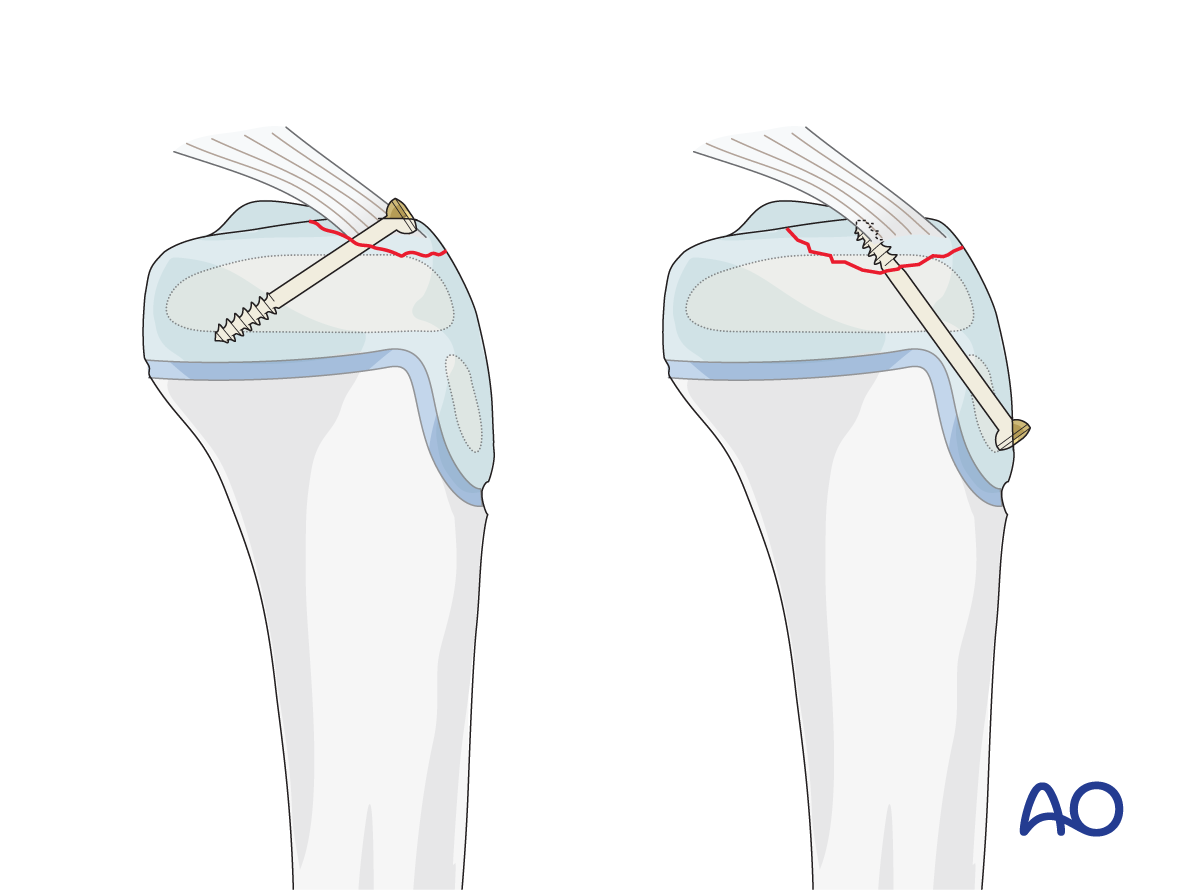

- Avulsion of tibial spine and posterior cruciate ligament

This includes detailed procedures on K-wire and screw fixation, external fixation, plate fixation, in addition to nonoperative management with casting and splinting.

Suture fixation of an avulsed tibial spine and cerclage compression wiring of an apophyseal avulsion are also covered.